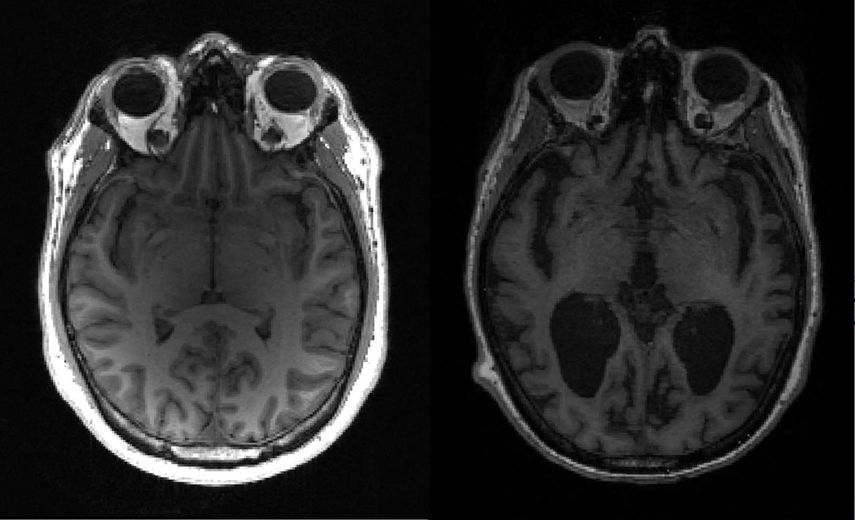

Sin embargo, y dado que los síntomas del SII afectan al intestino, los investigadores consideraban factible que los genes asociados con un mayor riesgo de la enfermedad se expresaran en estos órganos, pero encontraron que, en cambio, los genes alterados "se expresan predominantemente en el tejido cerebral o en los nervios dentro del intestino que reciben sus señales del cerebro".